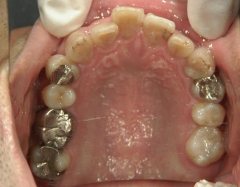

矯正歯科 治療前 右上4番、左右下4番 計3本抜歯し、叢生を改善

矯正_灰色.pngno.22_8175_治療前_上.jpg矯正_灰色.png

矯正_灰色.pngno.22_8175_治療前_下.jpg矯正_灰色.png